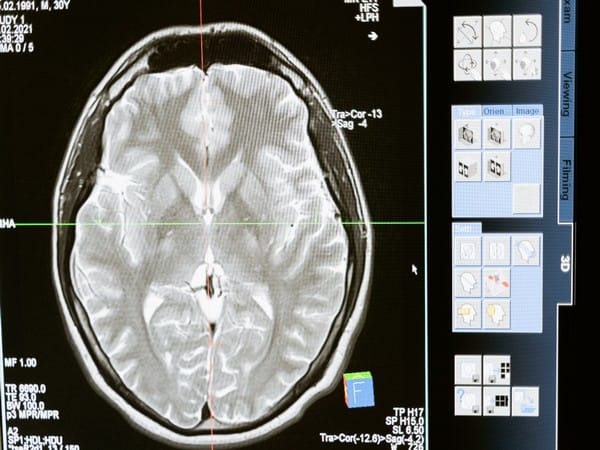

To find the different areas of neurons that become activated, Osterhout injected mice with pro-inflammatory agents, lipopolysaccharide or polycytidylic acid, which mimic bacterial or viral infection. She analyzed the areas of the brain that lit up in the brain scans.